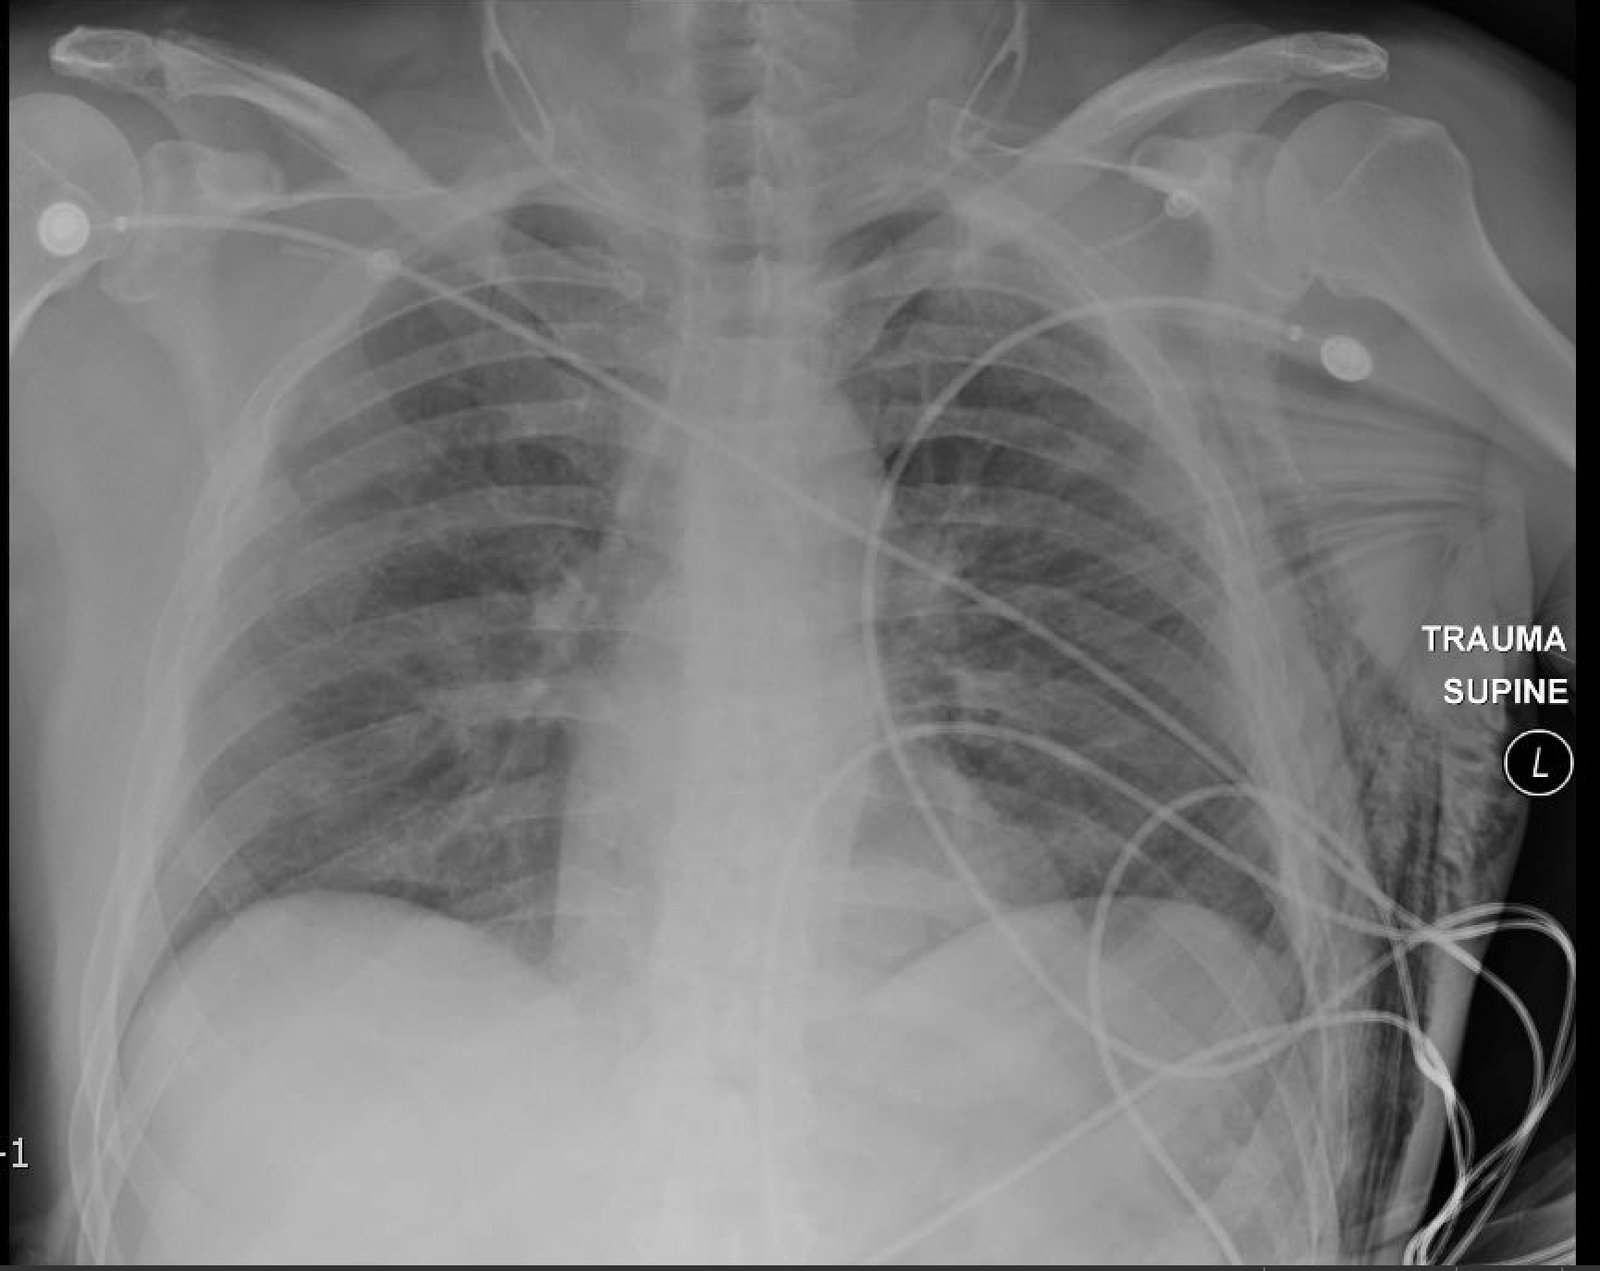

Plain film anteroposterior (AP) radiography of the chest shows left-sided subcutaneous emphysema (red arrow) with overlapping muscle striations of the pectoralis major (green arrow). After chest tube placement (blue arrow), AP chest radiography shows persistent left-sided subcutaneous emphysema (red arrow). CT of the chest shows pneumomediastinum (blue arrow), left apical pneumothorax (pink arrow), and subcutaneous emphysema (red arrow) at the level of T2. At the level of T6, rib fractures can be visualized on the CT (yellow arrow). At the level of T8, left sided pneumothorax is also seen (pink arrow) as the absence of lung tissue on CT.